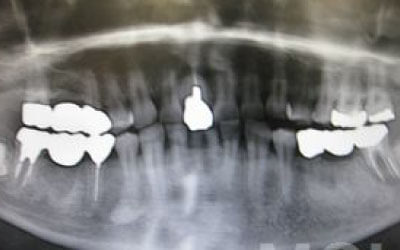

噛み合わせの力の60%以上がこの2本の奥歯で支えられているため、ここをしっかりとインプラントで治療するのが理想的です。